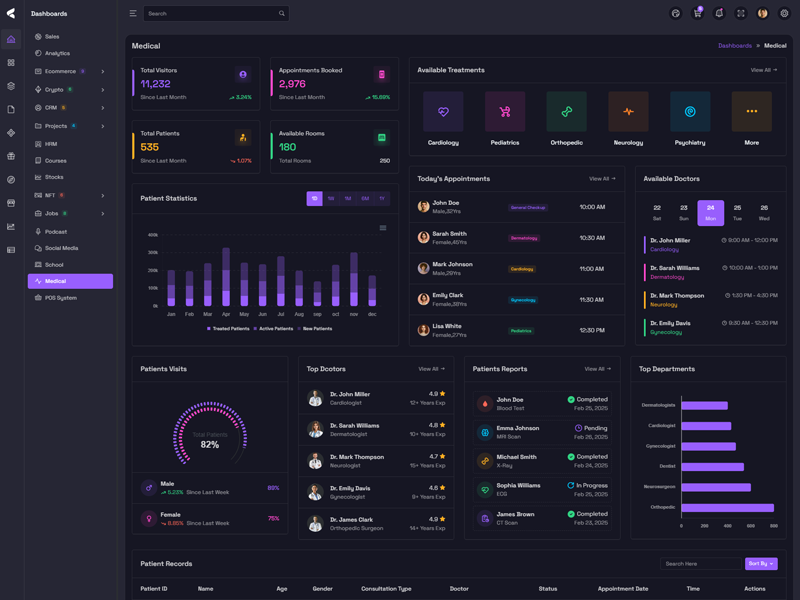

Vyzor Premium Tailwind CSS Admin Template

Vyzor – Create sleek, professional dashboards with ease using this customizable admin template. Skip complex coding with ready-to-use HTML, SCSS, CSS, and JS components. Build stunning, intuitive dashboards in minutes.